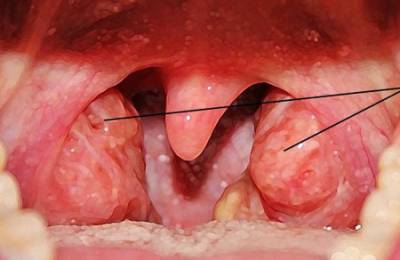

Нет нужды паниковать, болезнь только начинает проявляться. Возьмите зеркало, поднесите его ко рту и постарайтесь рассмотреть все тщательно.

Безусловно, вы можете хорошо увидеть малейшие оттенки недуга, более того именно вам под силу точно определить что же на самом деле являет проблема, и что с ней делать.

Вы можете найти небольшие пятна красноватого цвета, либо другие, более темные или белесые – это именно они являются причиной заболевания, а именно воспалительные процессы, которые возникают по причине инородных агентов.

Если болят гланды, следует пойти на прием к ЛОРу. Врач проверит миндалины, посмотрит, есть ли налет, прощупает их с внешней стороны. Бывает, пациенты интересуются: «Почему больше воспалена правая миндалина?»